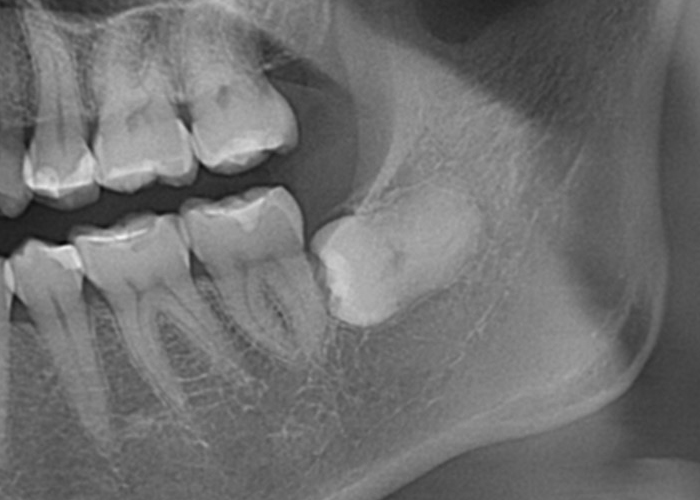

親知らずの生え方

半埋伏智歯(部分的に露出している)

半埋伏とは、親知らずの一部が歯肉の下に埋まっており、一部が口腔内に露出している状態を指します。

露出している部分には、歯垢や食物がたまりやすくなり、炎症や感染、虫歯のリスクが高まる場合があります。

また、半埋伏の親知らずは、周囲の歯や歯肉に圧迫を与え、痛みや不快感を引き起こすこともあります。

さらに、半埋伏の親知らずが隣接する歯に対して圧力をかけることで、歯列の乱れや移動が起こる場合もあります。

完全埋伏智歯(歯茎に完全に埋まっている)

完全埋伏とは、親知らずが完全に歯肉の下に完全に埋まっている状態を指します。

この場合、親知らずは通常、レントゲンやCTスキャンなどの画像検査でのみ確認できます。

完全埋伏の親知らずは、周囲の組織に直接的な問題を引き起こさない場合もありますが、将来的に問題を引き起こす可能性があります。

そのため、定期的な口腔検診や画像検査が重要です。

骨性完全埋伏智歯(骨に完全に埋まっている)

この場合も親知らずは通常、レントゲンやCTスキャンなどの画像検査でのみ確認できます。